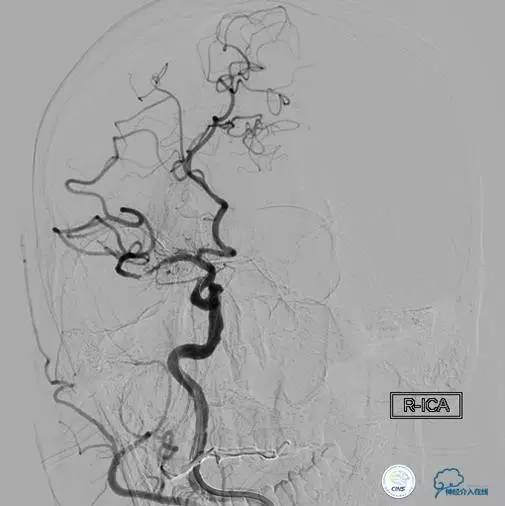

患者:徐××,男,62岁,主诉“右侧肢体活动不灵伴意识障碍3h”,于2015年6月5日入院。

现病史:患者始于3h起床后独自行走,述头晕,行走约10余米后突然摔倒在地,呼之不应,右侧肢体活动不灵,小便*禁失**,无呕吐、肢体抽搐,急打我院“120”急救电话来我院就诊,行颅脑CT检查未见出血,考虑为“急性脑血管病”。

入院查体:T35.7℃,P50次/分,R16次/分,BP99/73mmHg。神志不清,精神烦躁,双肺呼吸音粗,未闻及干湿性啰音,心率50次/分,律齐,未闻及病理性杂音。腹软,压痛及反跳痛检查不合作。双侧瞳孔等大等圆,大小约2mm,光反射迟钝,双眼球活动检查不合作,无眼震,咽反射、软腭动度检查不合作,双侧额纹对称,双侧鼻唇沟对称,口角无歪斜,伸舌、鼓腮检查不合作。右侧肢体肌张力下降,肌力0级,左侧肢体肌张力正常,肌力5级。左侧肢体腱反射(+),面部及肢体感觉检查不合作,右侧巴宾斯基征、奥本海姆征、查多克征(+)。

NIHSS评分:19分。

患者时间窗内,发病3h开始静脉溶栓。rt-PA9mg/kg,70mg,7mgIV;63mg微量泵注入1h。期间患者症状改善不明显。观察时间后,仍无改善。遂介入交接治疗。

2015-06-05脑血管造影:左侧颈内动脉闭塞。

评估患者侧支循环,考虑患者发病时间超过6个多小时,未行血管内治疗。